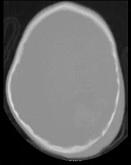

- 单项选择题男,3岁, 头颅被球击中,请结合CT图像, 选择最可能的诊断是 ( )

A、高血压性脑出血

B、脑结核

C、脑挫裂伤血肿形成

D、动脉瘤破裂出血

E、血管畸形